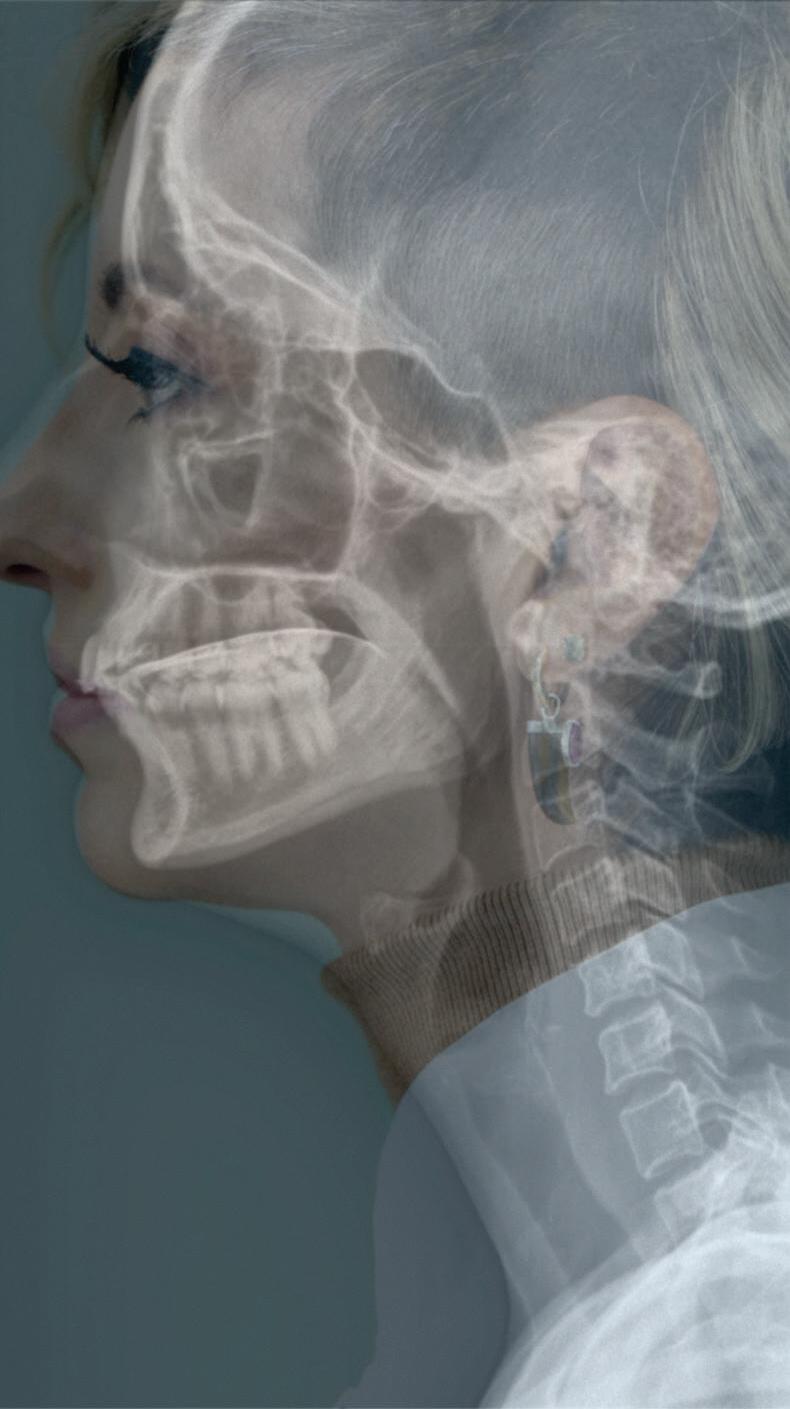

Fig. 1-2. Demonstração das estruturas envolvidas no processo da deglutição nas visões (a) lateral e (b) anteroposterior na imagem radiográfica.

Fig. 1-3. Demonstração das fases da deglutição em visão lateral nas imagens de videofluoroscopia. (a) Fase preparatória oral: incisão dos dentes na bolacha com a raiz de língua elevada, véu palatino abaixado e via aérea aberta; (b) fase preparatória oral: bolo alimentar na porção central da língua com a raiz de língua elevada, véu palatino abaixado e via aérea aberta; (c) fase oral: ejeção do bolo para a região da orofaringe com o movimento anteroposterior de língua e via aérea aberta; (d) fase faríngea: fechamento do véu palatino, elevação da laringe e do osso hioide, PPF = parede posterior de faringe.